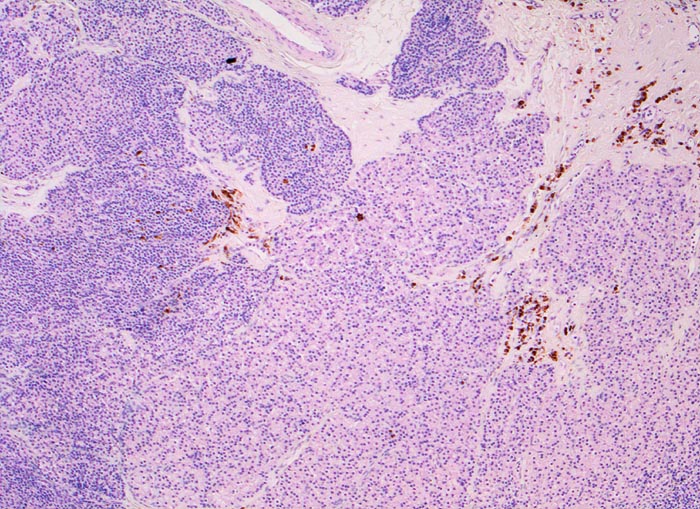

Morphologisch besteht bei sHPT eine Hauptzellhyperplasie. Makroskopisch findet sich eine meist ungleich ausgebildete Vergrösserung aller Nebenschilddrüsen. Die Grösse der Drüsen entspricht der Schwere und der Dauer des Stimulus. Die im früheren Stadium gefundene diffuse Hyperplasie mit Ersatz des Stromas und der Fettzellen durch chronisch stimulierte Hauptzellen (> 558) (> 559) geht im späteren Stadium in eine noduläre Hyperplasie („Pseudoadenome“) über (> 2358). Die regulierte Anpassung der Nebenschilddrüsen kann in eine Autonomie übergehen (tHPT) (> 3704). Morphologisch besteht in diesem Fall eine unregelmässige noduläre Hyperplasie. Gelegentlich entwickelt sich beim tHPT ein dominanter Knoten, der morphologisch nicht von einem Adenom bei pHPT unterscheidbar ist.

• Knotige vergrösserte Nebenschilddrüse. Abgrenzung der einzelnen Knoten durch breite Fibrosebänder.

• Hyperplasie lipidarmer Hauptzellen.

• Areale mit oxyphilen Zellen.

• Verminderter Fettgehalt (<<35%). Für normale Nebenschilddrüsen gilt: